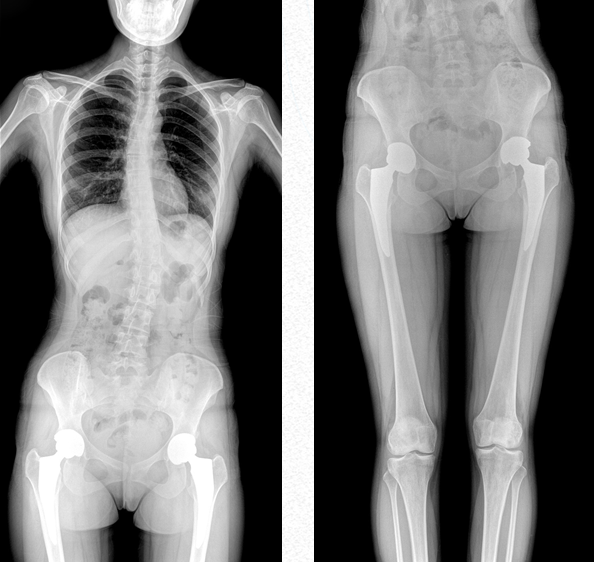

作为医疗机构普放的多功能诊断需求进行专业设计的新一代智能影像设备,普爱医疗PLX8600是一款超大视野多功能平板动态DR,17*34英寸动态平板,整板拍摄不拼接,呈现更准确的长骨影像。它在真正意义上实现了多科室、多功能应用,如各类常规的X线检查、消化道检查、骨科检查、妇科、儿科检查等。

超大视野范围,一次成像不拼接,减少拍片次数,缩短拍摄时间,降低患者的辐射剂量吸收

全脊柱成像

用于全脊柱摄影,为临床提供准确的二维影像,支持全脊柱斜位透视诊断,方便对椎弓根峡部进行观察,诊断腰椎是否滑脱。如:先天性脊柱侧弯、后凸畸形、多节脊柱创伤等。此外,大视野动态透视功能,在全脊柱脊髓造影的临床应用中也颇具优势。

双下肢成像

用于创伤弓|起的四肢骨折,进行较长髓内钉术前诊断、术后复诊的大视野摄影。

PLX8600大视野动态平板DR可摄影、可透视、可造影,临床适用范围广泛,满足临床拍摄需求。与市面常规多张摄影再软件拼接的DR相比,PLX8600大视野动态平板DR解决了拼接图像存在密度不均匀,拼接处图像配准和放大效应等问题,一体式的机架,摆位简单快捷 ,具有畸变率低、测量精度高、图像质量好、无拼接痕迹等优点。这款DR不仅融合了市面上17*17英寸动态DR的功能,除此之外它独具特色的17*34英寸超大动态视野范围,给临床应用带来较高价值,减轻医院设备投入成本,获得更大收益。